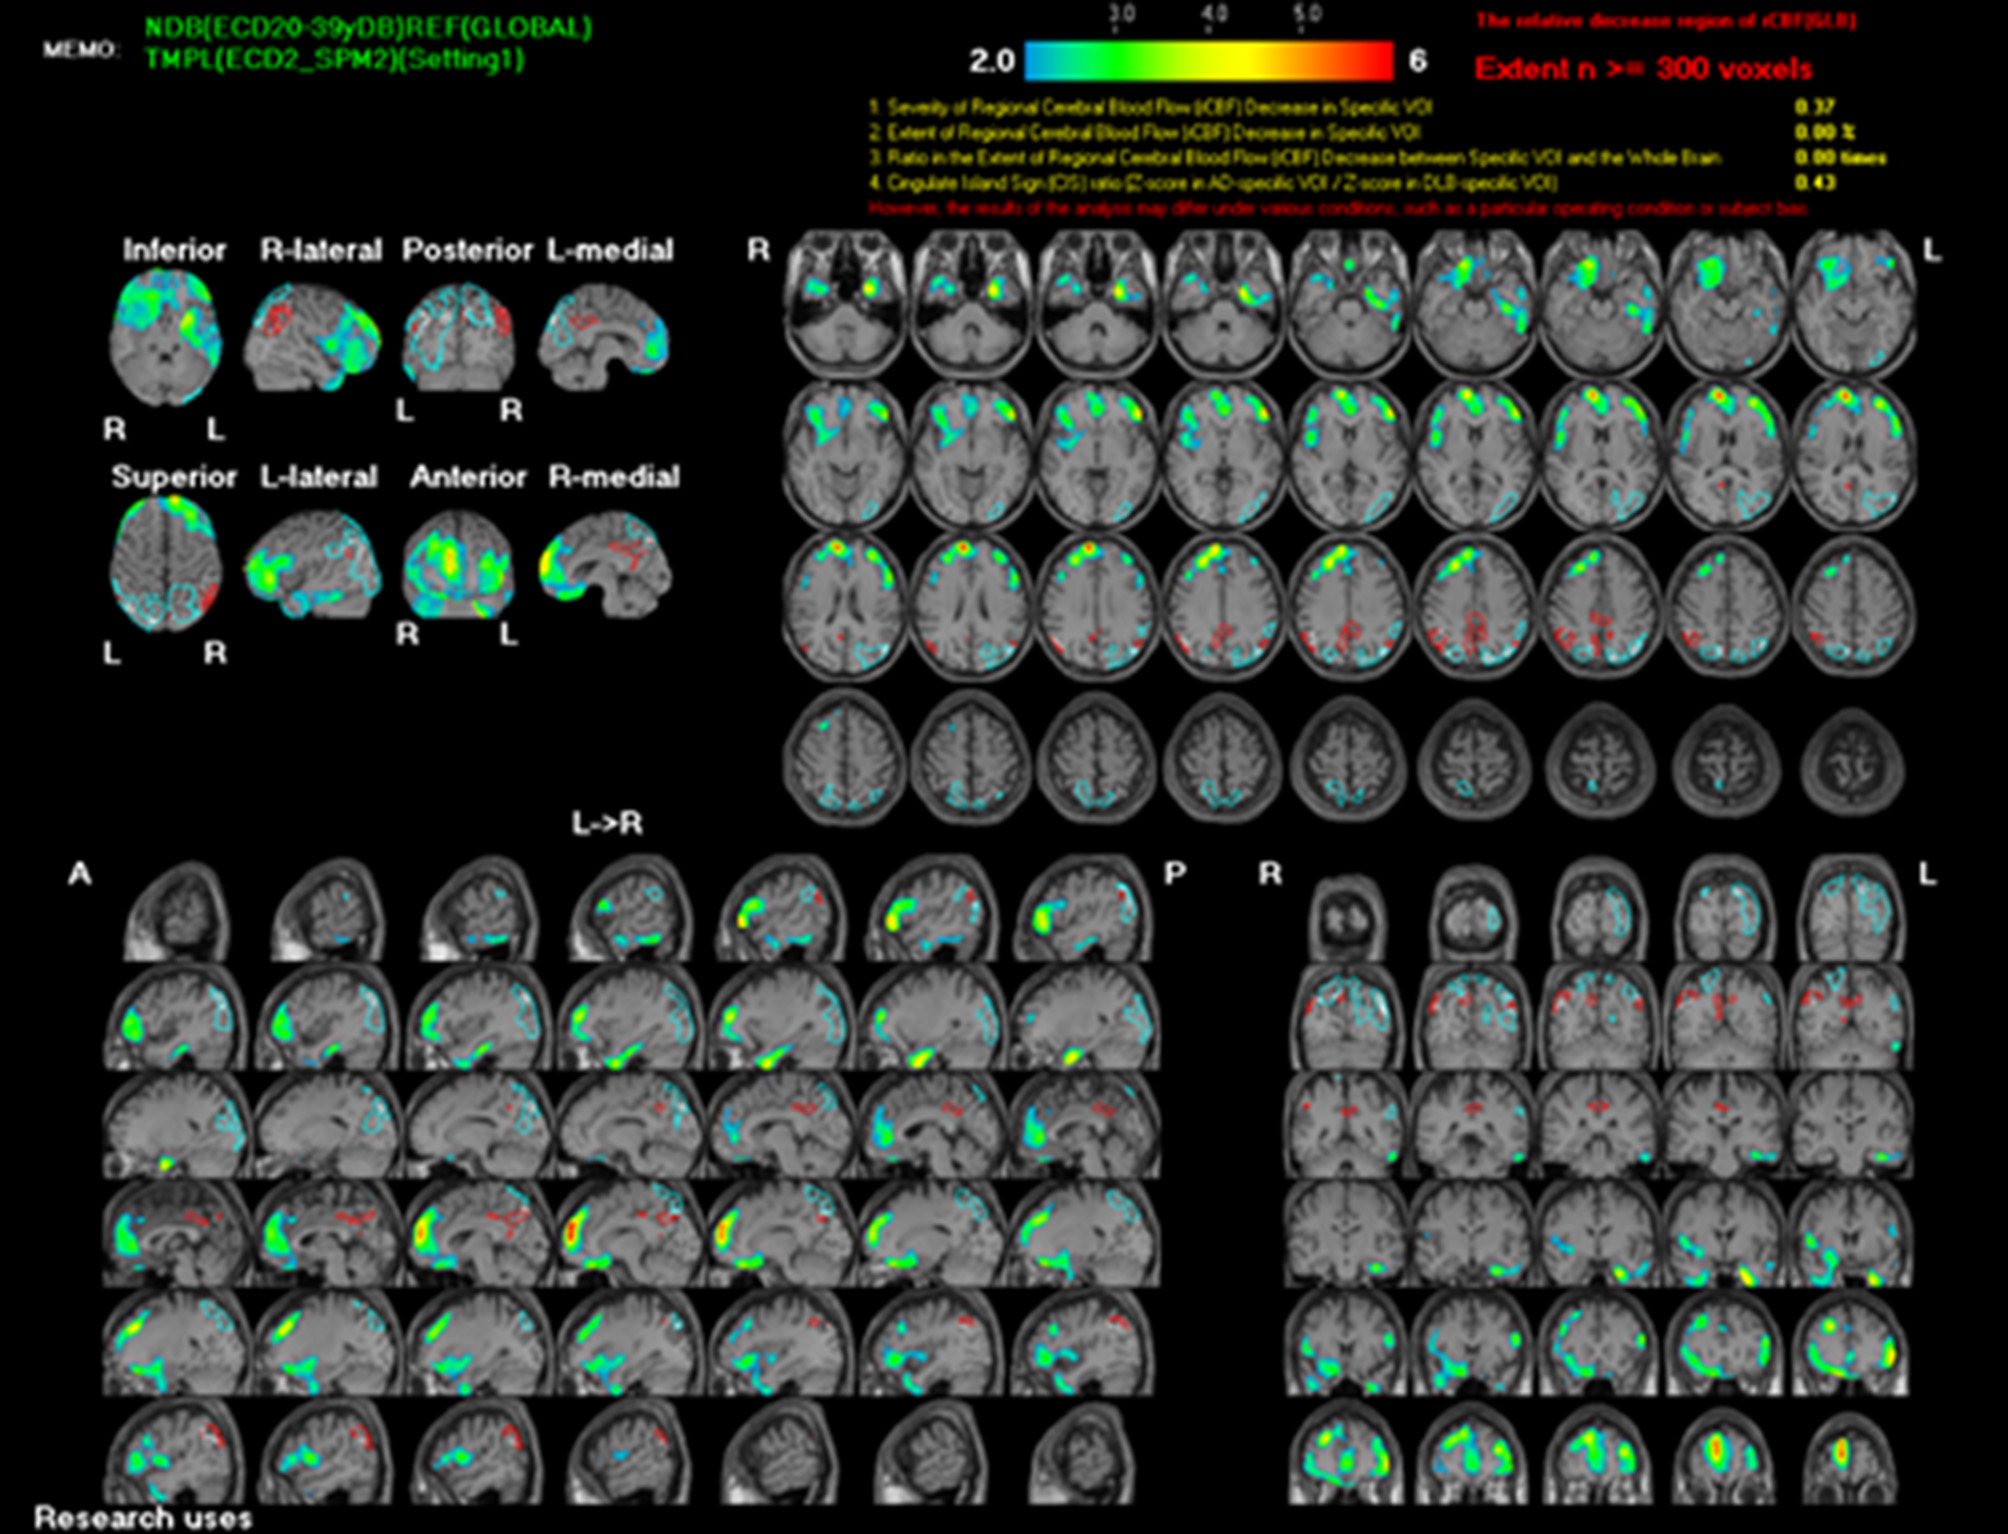

To rule out structural lesions, a brain MRI with contrast was also performed. The MRI showed multiple levels of abnormal progressive luminal vessel stenosis involving bilateral ICA supraclinoid segments, bilateral ACA A1 segments, and bilateral MCA M1 segments (Figure 1). The Moyamoya disease was impressed. Tc-99m ECD brain perfusion SPECT was also carried out to evaluate cerebral circulation, which showed mild to moderate hypoperfusion in bilateral frontal and left temporal regions (Figure 2). CSF analysis was within normal limits. After administering 20 mg dexamethasone for 5 days, the patient's symptoms of paroxysmal choreoathetosis and dystonia recovered rapidly (Supplementary Video 1, after). The long-term use of methimazole was recommended, and the patient was then referred to a neurosurgeon for further surgical intervention of revascularization.

Figure 2

Tc-99m ECD brain SPECT scan shows mild to moderate hypoperfusion in bilateral frontal and left temporal regions.